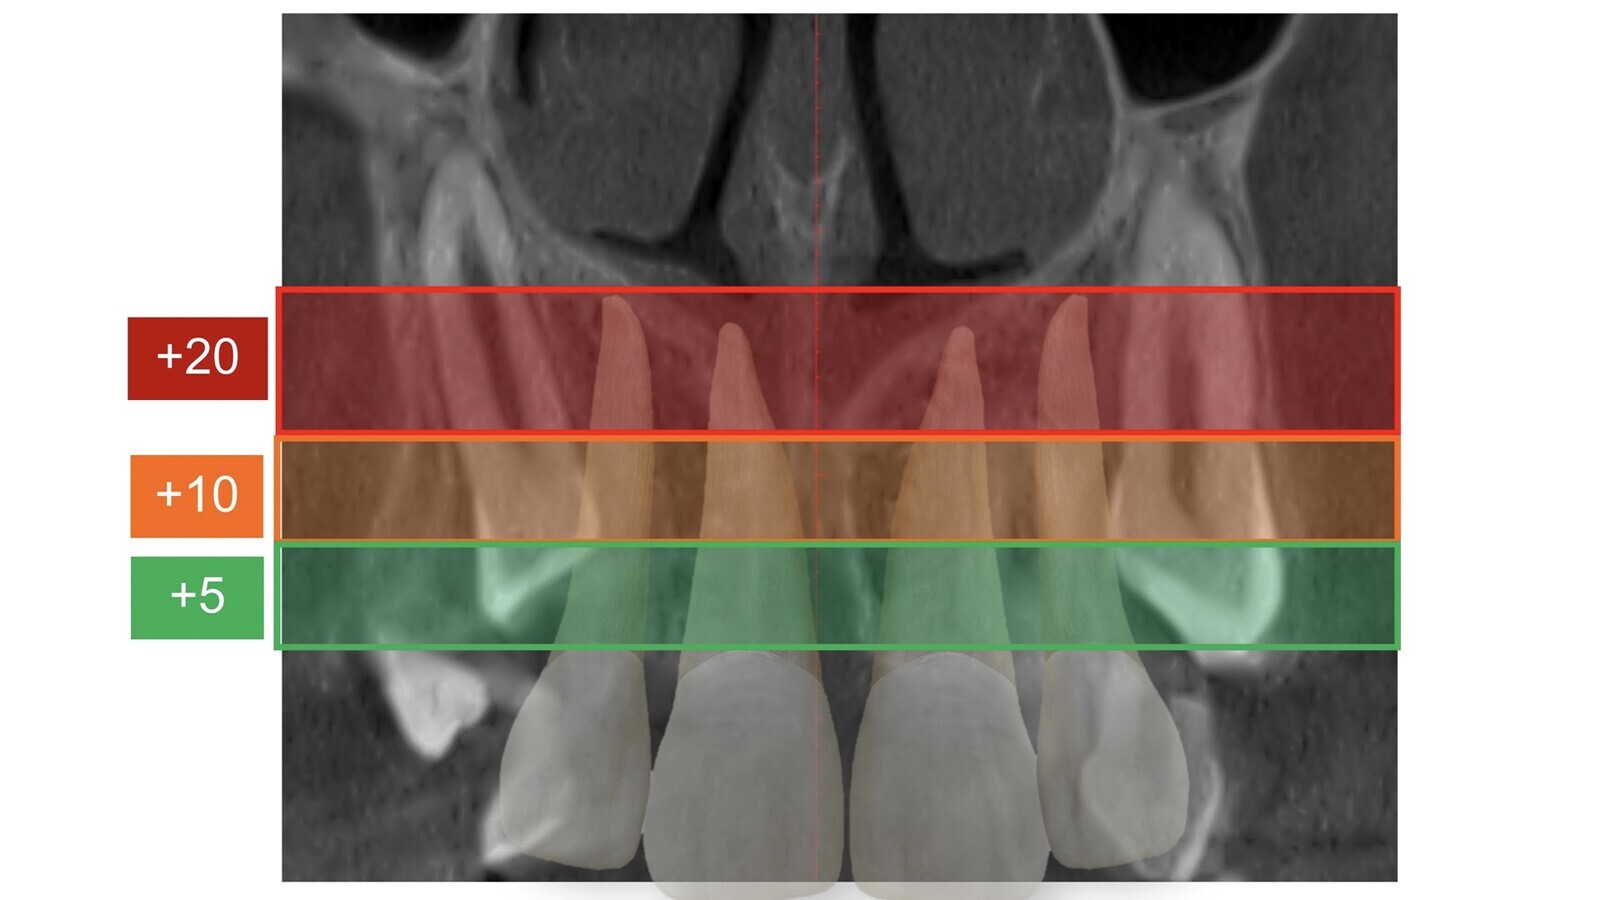

Diagrama que muestra que los cortes oclusales pueden tener una relación armoniosa de vecindad entre el canino con los incisivos y premolares o presentar signos de reabsorción externa de las raíces vecinas.

Los cortes transversales de los caninos nos orientan sobre su verdadera inclinación. Los cortes oclusales (figura 9) muestran la relación de vecindad del canino con los incisivos y premolares y si ésta es armoniosa (espacio de seguridad suficiente alrededor de la corona del canino) o presenta signos preocupantes de reabsorción externa de las raíces vecinas.

Figura 9. Los cortes oclusales muestran la relación de vecindad del canino con los incisivos y premolares y si ésta es armoniosa o presenta signos preocupantes de reabsorción externa de las raíces vecinas.

Sobre estos cortes oclusales también establecemos áreas poligonales de mejor (área I) a peor pronóstico (área III), según delimiten las zonas normales de emergencia canina o zonas muy alejadas. La suma de la angulación y la valoración objetiva de cada área ya nos va orientando sobre la mayor o menos dificultad del caso.

Figura 10. Primera valoración espacial tridimensional de los cortes oclusales.